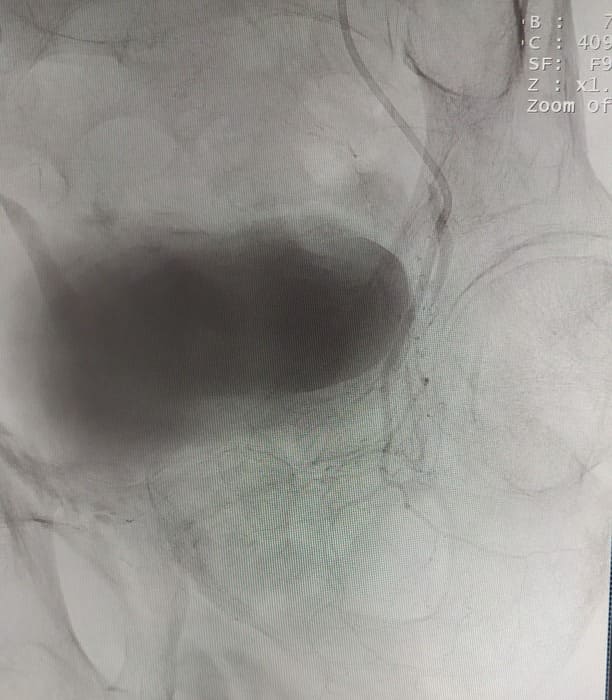

До нас звернувся пацієнт 79 р. Зі скаргами на періодичну затримку сечі. Скарги наростали поступово, на протязі кількох місяців. Особливістю даного випадку було те, що чоловіку в 2006 році вже було виконано через-міхурове видалення передміхурової залози. Проте частки що лишились дали ріст нової тканини. І за ці роки виросла нова патологічно збільшена залоза (майже 5см в діаметрі). Після дообстеження було виключено злоякісну природу цього утвору і ми вирішили перейти до операції.

Зазвичай люди літнього віку мають вражені атеросклерозом та звивисті, внаслідок гіпертонічної хвороби судини. Цей випадок не був виключенням, тому нам довелося докласти максимум зусиль, використати високотехнологічне обладнання та інструменти, щоб віднайти цільові судини. На диво, незважаючи на попередню операцію, судинний малюнок рецидивної простати збігався з тим який буває у не оперованих пацієнтів. Тому нам вдалося їх чітко визначити з обох сторін та заповнити емболами. Це доволі кропітка праця, адже щоб викликати ішемію, необхідно поступово виключити кровоплин в усій тканині залози. Полегшувало операцію лише відсутність перетоків артерій на сусідні органи. Це дозволило нам безпечно емболізувати, не боячись негативних наслідків та ускладненнь.

Ми все ж терпляче чекали на результати ультразвукової діагностики. І були дуже раді побачити, що за три тижні розмір залози зменшився в три рази.